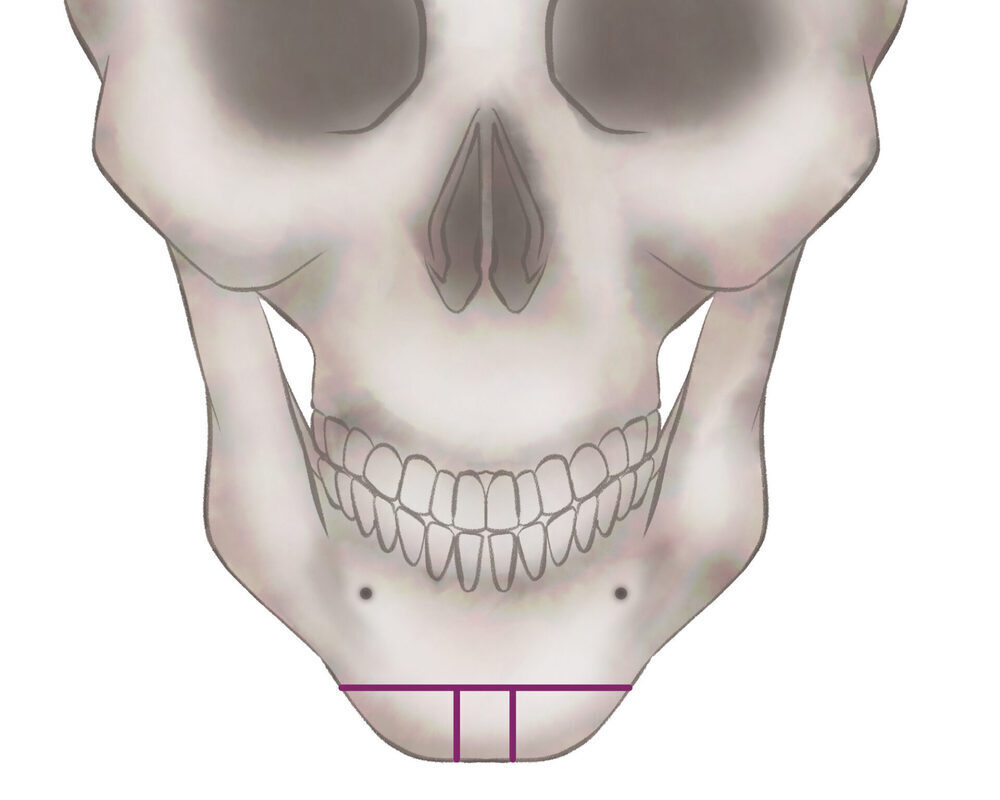

オトガイ骨切り(中抜き)

1.切開線をデザインします

2.骨を切除します

3.骨を移動させ段差を削ります

4.プレートで固定します